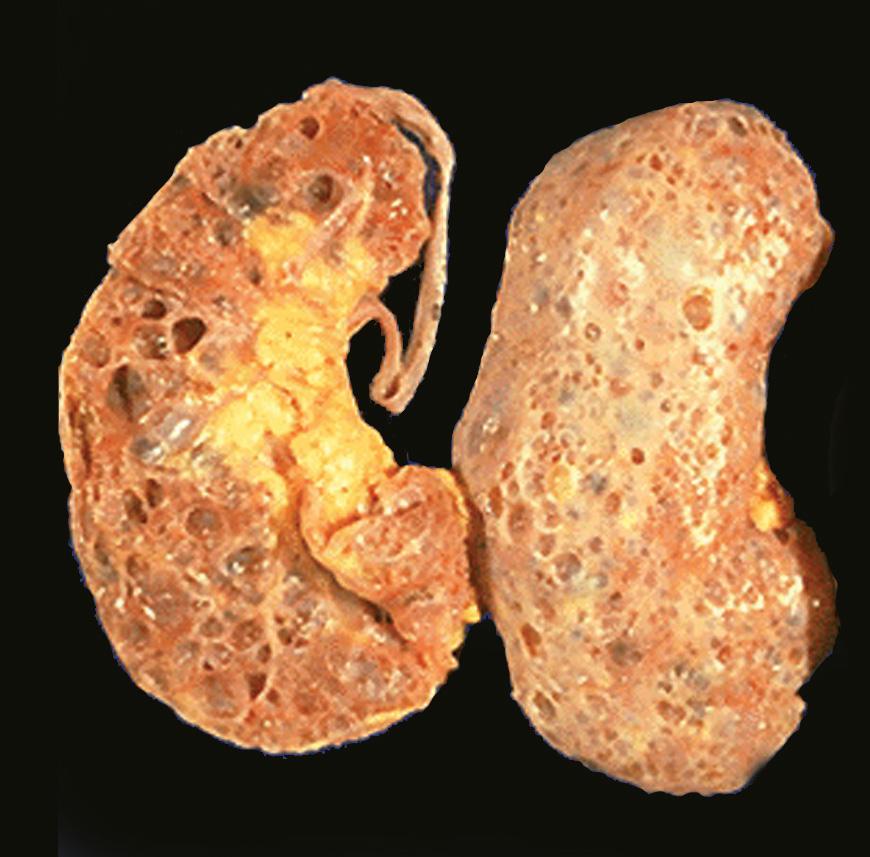

Over the past two decades, the number of Americans with kidney failure has quadrupled to more than 808,000, now being treated at a cost of $29 BILLION annually via dialysis (69%) and transplants (31%). Each year, over 130,000 Americans are newly diagnosed with End Stage Renal Disease (ESRD) and put on dialysis. After five years on dialysis, only about 25% of patients are still living. After 10 years, less than 8% are still alive.

The only reason your kidneys are failing is because they are trying to filter blood that is more like toxic sludge. If you clean up your lifestyle, improve your food program, and flush out your elimination organs (especially your bowel, your liver, gallbladder, and of course, your kidneys) your kidneys and body will heal themselves.